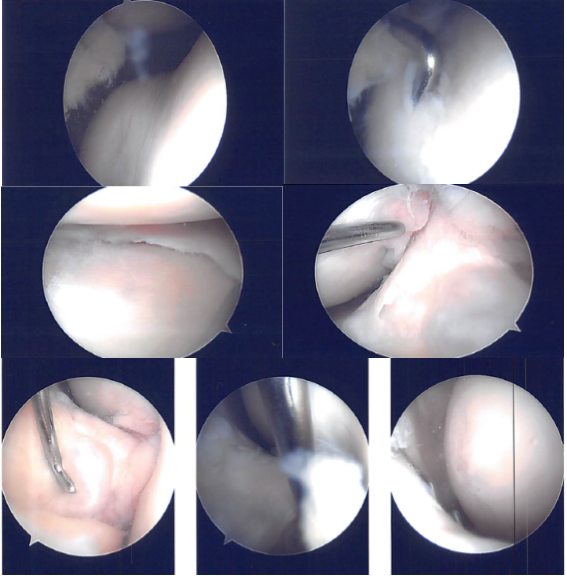

A lateral working portal was made through left-sided Incision. The scope was entered into a patellofemoral joint where arthritis was found on the medial and lateral facet of the patella as well as in the trochlea.

The scope was entered into medial femoral condyle where medial femoral condyle arthritis was found. There was a medial meniscus tear along the anterior body. The scope was entered into the intercondylar notch where ACL was Intact. The scope was entered into the lateral tibiofemoral Joint.

A horizontal flap tear of the right anterior margin of the posterior body of the lateral meniscus along with the medial fraying of the medial margin of the lateral meniscus was found. Medial entry portal was made with direct access to the lateral meniscus. The scope was entered and findings were reconfirmed.

Intraoperative Images

The medial meniscectomy was performed using a shaver. Medial femoral chondroplasty was also confirmed using a shaver. Cyclops lesion was found on the ACL lateral Insertion. The cyclops was then excised using a shaver.

The scope was entered into the lateral compartment where the tears were reconfirmed. Excision of the medial horizontal flap was done using straight biter.

Cribbing of the lateral meniscus was done using a shaver. Balanced margins were achieved. There was no arthritis in the lateral femoral condyle. Now the attention was focused onto the patellofemoral joint.

Chondroplasty of the patellar medial and lateral facet as well as the trochlea was performed. There were grade 2 to grade 3 lesions. There was a medial shelf plica which was excised completely.

Final findings were checked and reconfirmed from the other portal also. The final pictures were saved. The knee was irrigated thoroughly. Closure was done using nylon #4-0.